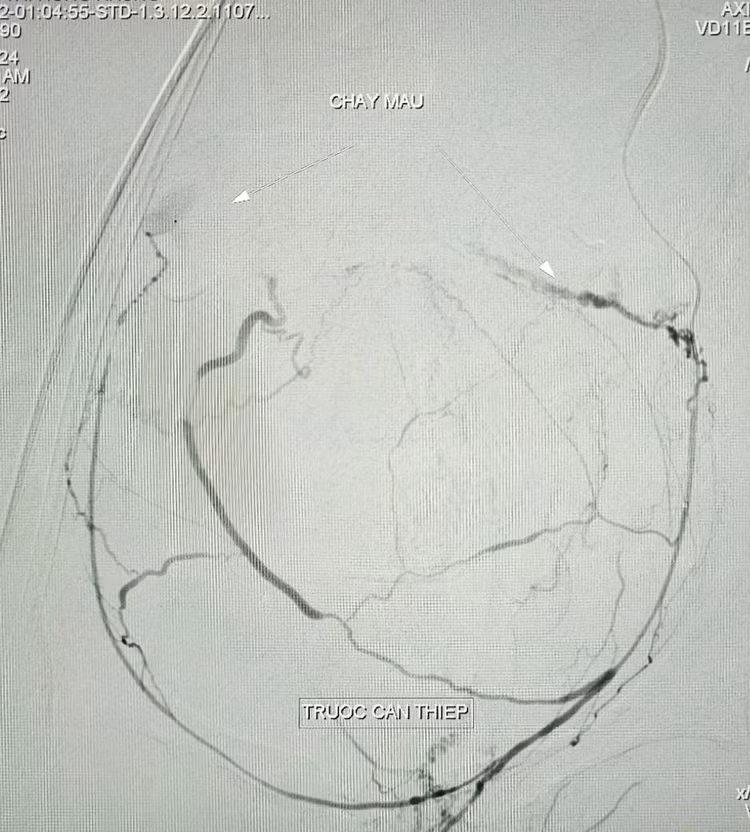

Kết quả chụp cắt lớp vi tính ổ bụng có cản quang ghi nhận hình ảnh ổ thoát mạch.Bệnh nhân có chỉ định chụp và nút mạch điều trị cầm máu các tạng số hóa xóa nền cấp cứu (DSA).

BS.CKII. Trần Công Khánh, Phó khoa Chẩn đoán hình ảnh và ê-kíp thực hiện, kết quả ghi nhận tăng sinh nhiều nhánh động mạch chậu trong hai bên, tổn thương co thắt mạch kèm ổ thoát thuốc vùng tiểu khung được cấp máu từ nhánh chậu trong trái, xác định vị trí và tiến hành bơm tắc bằng hỗn hợp keo, chụp kiểm tra ghi nhận không còn ổ thoát mạch, sinh hiệu bệnh nhân ổn định được chuyển khoa Hồi sức tích cực – Chống độc tiếp tục theo dõi.

Trưa ngày 02/10/2024, bệnh nhân có dấu hiệu xuất huyết nội tái phát và được chỉ định chụp cắt lớp vi tính bụng có cản quang kiểm tra phát hiện ổ thoát mạch, các bác sĩ tiến hành chụp và nút mạch điều trị cầm máu các tạng số hóa xóa nền (DSA) lần thứ hai. Kết quả ghi nhận hình ảnh thoát mạch được cấp máu từ nhánh động mạch mạc treo tràng trên, xác định vị trí tiến hành bơm tắc bằng hỗn hợp keo, thủ thuật tiến hành 40 phút, bệnh nhân ổn định tiếp tục hồi sức tích cực.

| Hình ảnh chảy máu trên phim chụp trước và sau can thiệp - Ảnh BVCC |